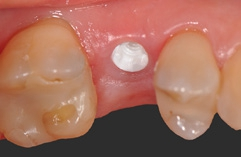

Definitive Eingliederung

Die mit dem Abutment verklebten Restaurationen konnten nun entnommen, Zementüberschüsse (Abb. 22) sicher entfernt und die Übergänge von Krone zu Abutment poliert werden. Für die definitive Eingliederung ist der für die Abutmentschraube vorgegebene Anzugstorque von 25 Ncm einzuhalten. Nach erneutem Auffüllen der Schraubenkanäle wiederum mit Teflonband wurden die Zugangskavitäten in ebenfalls üblicher Weise mit Komposit verschlossen. Das Ergebnis sind im vorliegenden Fall 2 metall- und zementfreie, verschraubte und reversible Einzelzahnrestaurationen (Abb. 23). Bei dem routinemäßig durchgeführten Follow-up 6 Monate nach Eingliederung zeigte sich eine an beiden Implantatpositionen reizlose Weichgewebssituation (Abb. 24a und b) und in den radiologischen Kontrollaufnahmen stabile periimplantäre Knochenverhältnisse (Abb. 25a und b).